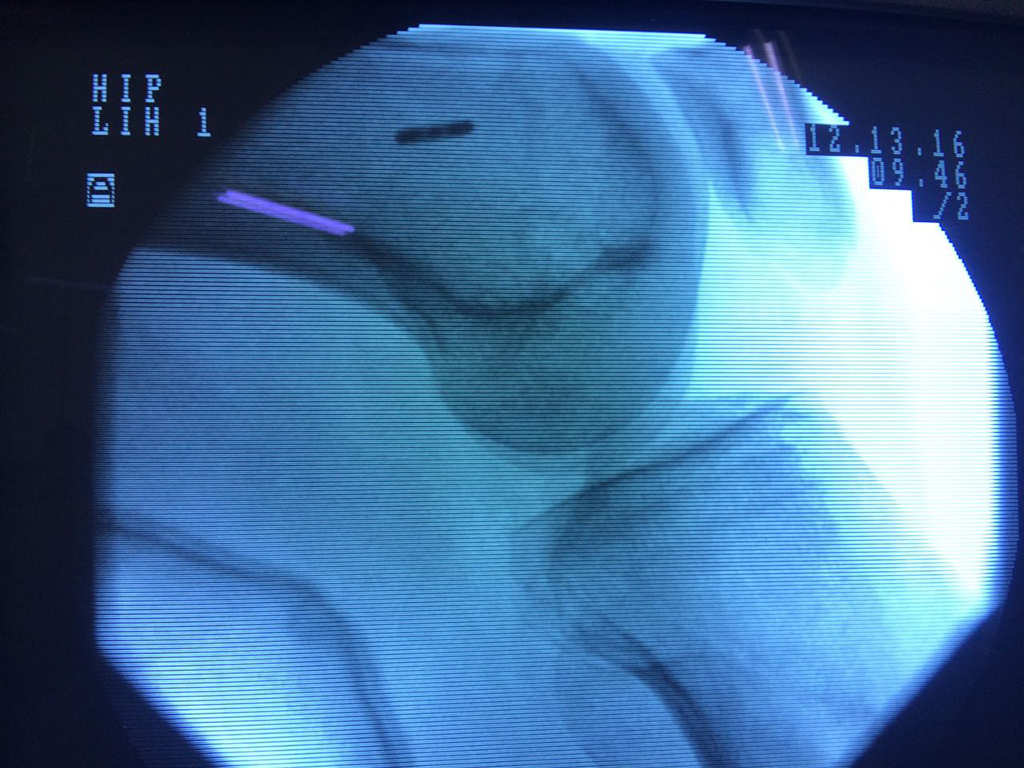

La artroscopia de rodilla es un cirugía en el cual la estructura interna de la articulación es examinada ya sea para realizar un diagnostico o para realizar un tratamiento, este procedimiento se realiza utilizando un instrumento parecido a un pequeño tubo llamado artroscopio.

La artroscopia se popularizo en 1960 y hoy en día es muy común en todo el mundo. Típicamente, es realizada por cirujanos ortopédicos de manera ambulatoria. Cuando se realiza de manera ambulatoria los pacientes pueden regresar a casa después de la operación, no se requiere quedarse en hospital.